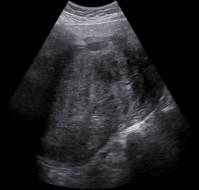

Advancements in obstetric imaging have profoundly enhanced the monitoring and management of pregnancies, particularly those identified as high risk. Among the variou..

Uteroplacental insufficiency—characterized by inadequate blood flow to the placenta during pregnancy—requires a thorough understanding of the underlying placental pa..

Uteroplacental insufficiency – characterized by inadequate blood flow to the placenta during pregnancy, necessitates an understanding of its underlying placental pat..